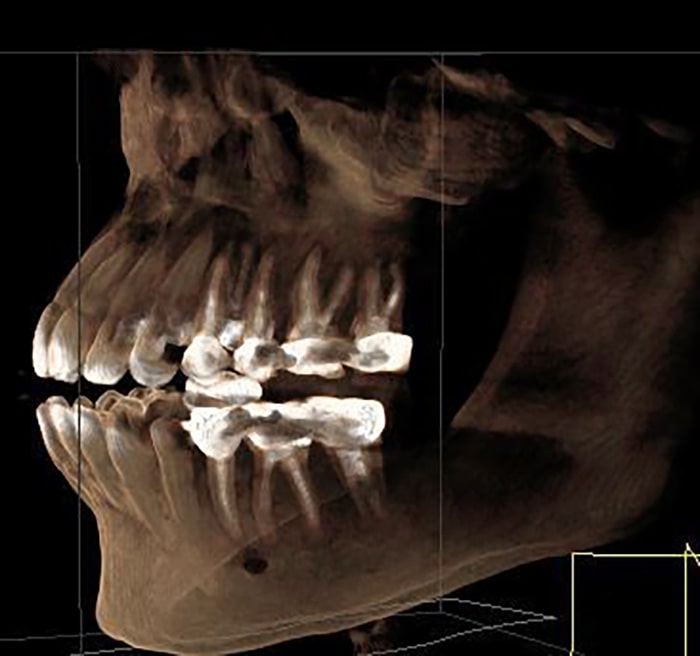

At Kamala Dental Super Speciality Hospital, Thiruvananthapuram, we utilize advanced Cone Beam Computed Tomography (CBCT) and 3D scanning technologies to obtain highly detailed images of your teeth, jaws, nerves, and surrounding structures. These cutting-edge tools empower our team to diagnose more accurately and plan treatments with greater precision - giving you safer, more predictable outcomes.

- Detailed, Clear Views: CBCT produces 3D images of bone anatomy, root canals, jaw joints, sinuses, and nerve pathways - far more informative than traditional 2D X-rays.

- Accurate Diagnosis: Detect hidden problems such as impacted teeth, root fractures, infections, and bone defects early.

- Evaluation of impacted or extra teeth

- Diagnosis of root canal anatomy & complex endodontic cases